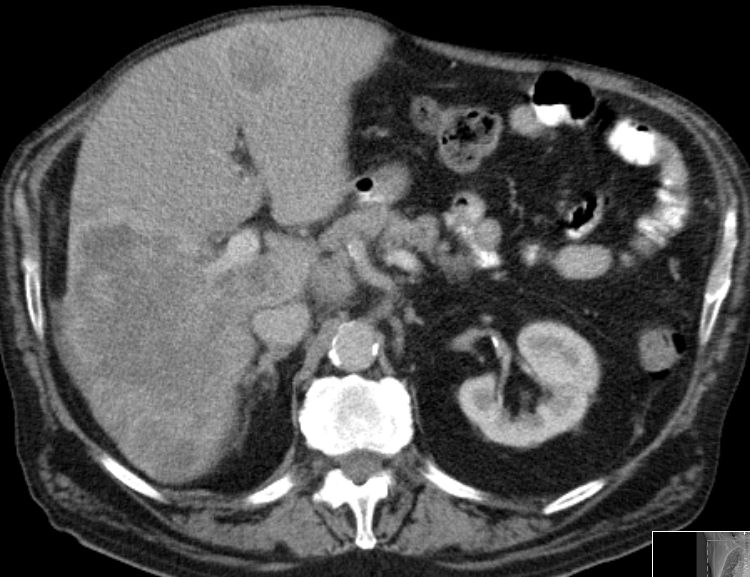

| CT | 79-jähriger Mann mit Raumforderung im rechten Leberlappen. AFP > 3000.![]() | ||